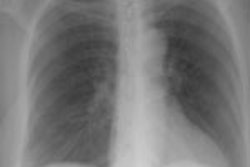

High Altitude Pulmonary Edema:

The patient shown below was an Intern who presented with shortness of breath after climbing Mount Rainer. The portable CXR revealed patchy alveolar airspace abnormalities predominantly confined to the mid and lower lung zones.